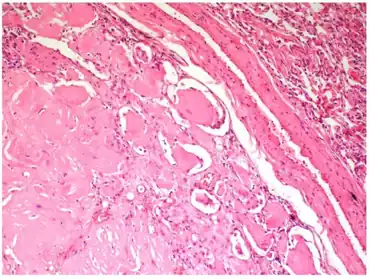

| Lesion with regular margins containing very hypocellular, keloid-type coarse collagen | |

Pulmonary hyalinizing granuloma is characterized by localized changes in lung architecture determined by deposition of hyaline collagenous fibrosis accompanied by sparse lymphocytic infiltrate that compresses and distorts the remaining bronchioles. A higher magnification, the mass is composed by hypocellular collagen lamellae.[3]